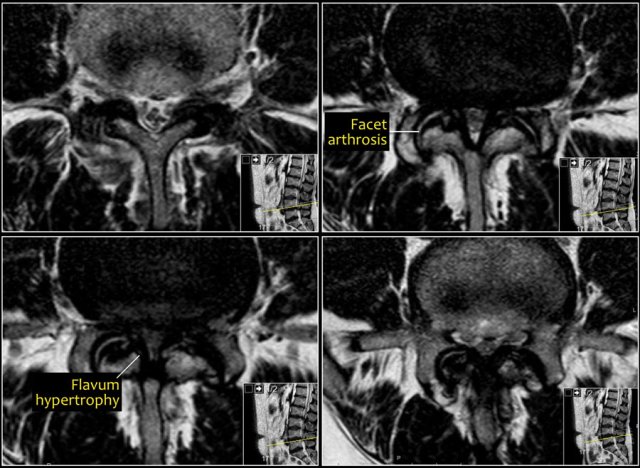

Here a patient with bilateral facet arthrosis resulting in narrowing of the lateral recess on both sides with nerve compression.

Scroll through the images.

• Bilateral facet arthrosis in combination with bulging of the disc and hypertrophy of the ligamentum flavum

Notice the short pedicles in combination with facet arthrosis and flavum hypertrophy.